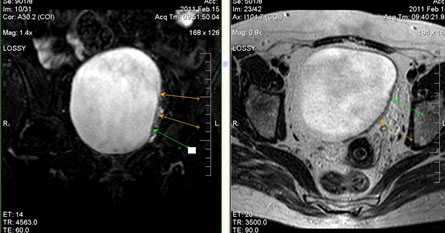

(Слева) Рентгенограмма женщины 37 лет с параплегией и микрогематурией в передней проекции: множественные камни в мочевом пузыре. Некоторые имеют индивидуальную криволинейную форму, что говорит о том, что они, возможно, сформированы вокруг инородных тел.

(Справа) КТ мочевого пузыря с контрастированием, аксиальный срез: множественные округлые кальцинированные камни, покрывающие нижнюю часть просвета мочевого пузыря. У пациента наблюдалась длительно текущая обструкция мочевого пузыря, вследствие доброкачественной гиперплазии простаты (ДГП).

(Слева) КТ с контрастированием, аксиальный срез: типичная картина коралловидного камня мочевого пузыря, который обычно состоит из дигидроксида кальция. Они чаще формируются в мочевом пузыре, нежели чем в верхних мочевых путях.

(Справа) МРТ мочевого пузыря, Т1-ВИ, аксиальный срез: множественные округлые очаги исчезновения сигнала в нижней части просвета мочевого пузыря, представляющие собой камни у мужчины с заметным увеличением предстательной железы. Конкременты мочевого пузыря гипоинтенсивны на Т1В и Т2В изображениях, вследствие диамагнитных свойств солей кальция.